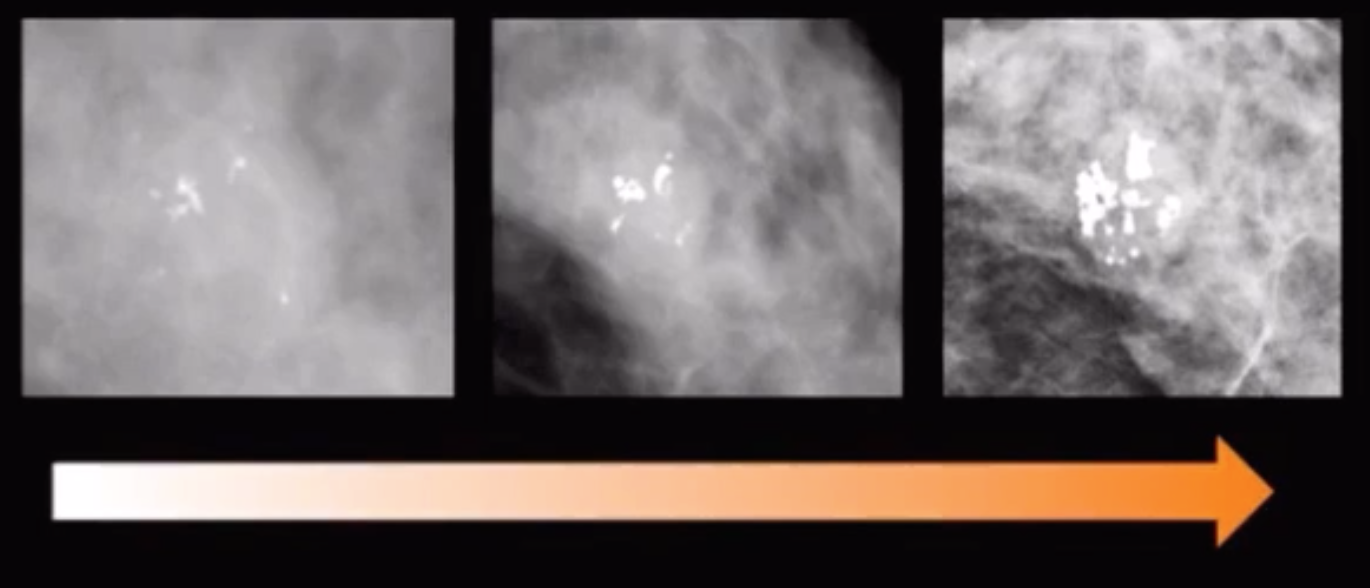

• Clustered/grouped round calcifications

• Baseline - BR3

• New from prior -BR4